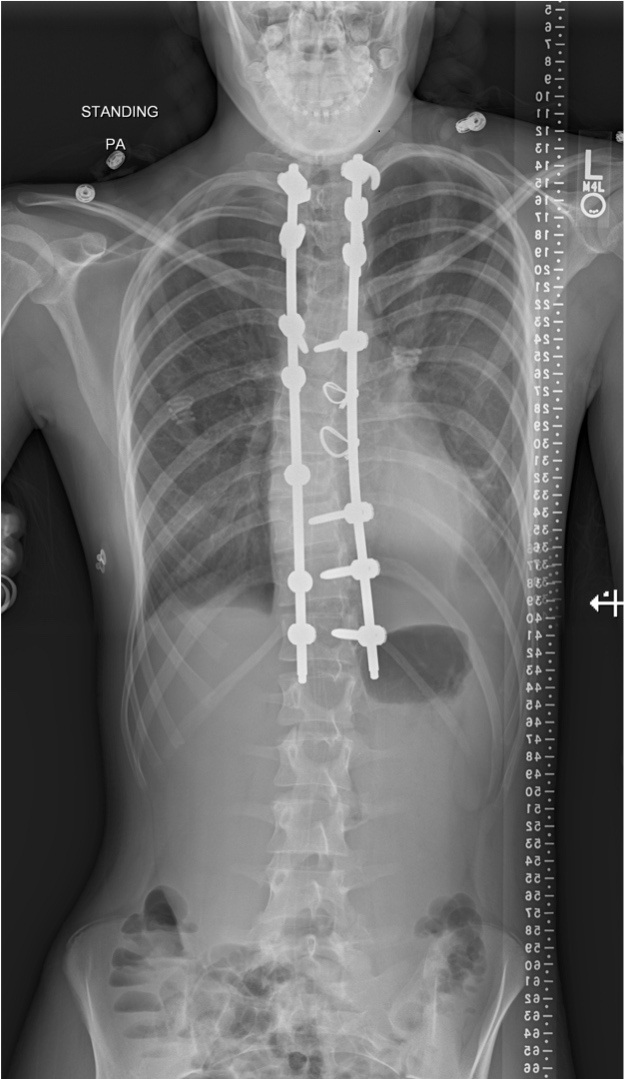

Posterior Spinal deformity correction and instrumented fusion surgery|Pune Spine Institute|Spine clinic in pune Spine centre in pune, Spine hospital in pune, Spine care in pune

Patient was treated with Posterior Spinal deformity correction and instrumented fusion surgery to correct the scoliosis.